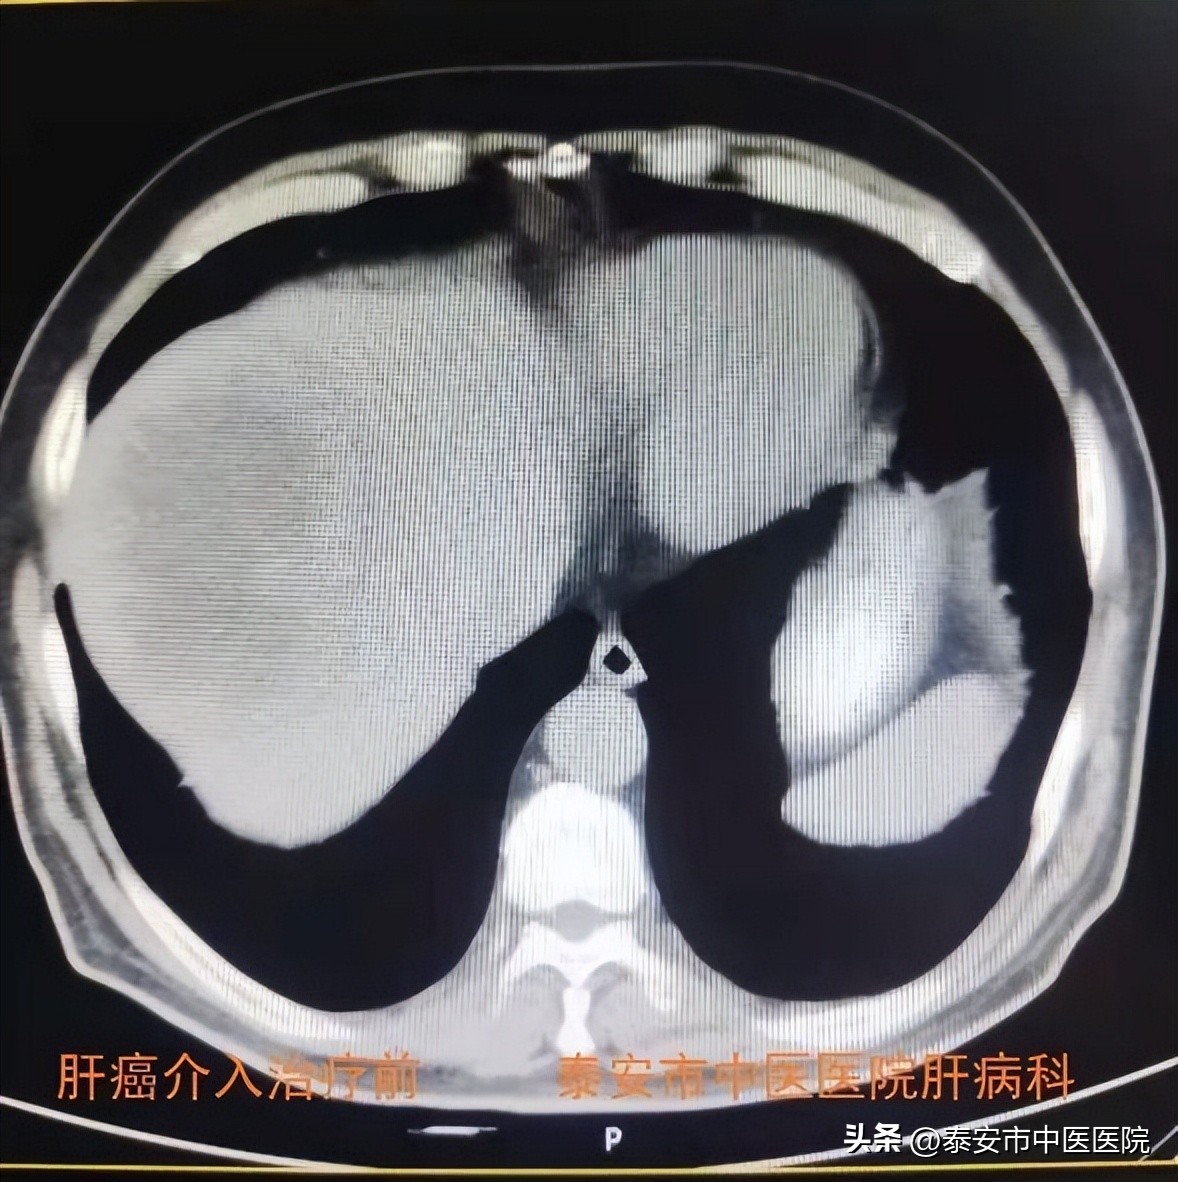

3.肝癌介入治疗

借助医院引进的 Philips最新一代霓彩系列大平板数字减影血管造影机(DSA) ,与介入科合作开展肝癌介入治疗。在数字减影血管造影机下,选择插管至肿瘤供养血管内,进行肝动脉灌注化疗(TAI)、肝动脉栓塞(TAE)、肝动脉化疗栓塞(TACE)等治疗,是控制肝癌生长及联合系统治疗的主要手段之一。